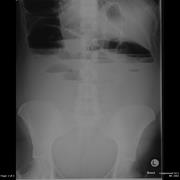

Caecum herniation through the Foramen of Winslow

Sarah F. Powell-Brett and others

Journal of Surgical Case Reports, Volume 2012, Issue 12, December 2012, rjs016, https://doi.org/10.1093/jscr/rjs016